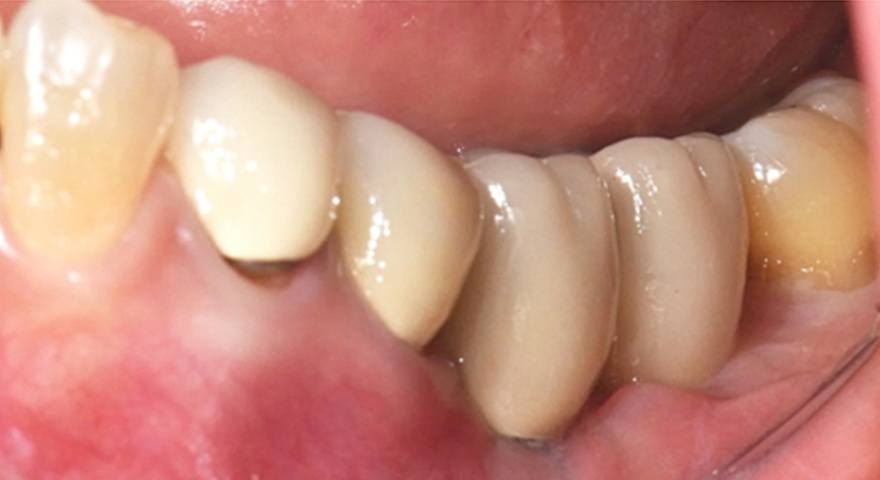

Рис. 2. (A) Пацієнт із виявленою необмеженою (non-contained) втратою кісткової тканини та оголенням імплантату з букального боку на момент встановлення імплантату. (B) Нанесення основного шару пастоподібного кісткового матеріалу перед внесенням гранульованого кісткового трансплантата. (C) Укладання колагенової мембрани з покриттям зони трансплантації — від букального до піднебінного боку — та фіксували за допомогою внутрішніх періостальних швів. (D) Через шість місяців після аугментації — візуалізується регенерація кістки з букального боку в ділянці раніше оголеної різьби імплантату.

Встановлення вузького імплантату та негайне навантаження з тимчасовою реставрацією в області правої нижньої щелепи

Діагноз: відсутній зуб # 44

План лікування:

44, Ø3.1X12мм імплантат INNO та негайна реставрація

44 SFIT Ti-Base та коронка Zircornia 1 місяць після операції

- Цей випадок показує вузьку установку імплантату в правій нижній щелепі.

- Імплантат був розміщений на місці зуба #44 з вузькими проміжками і тимчасова реставрація з акрилової смоли була негайно встановлена.